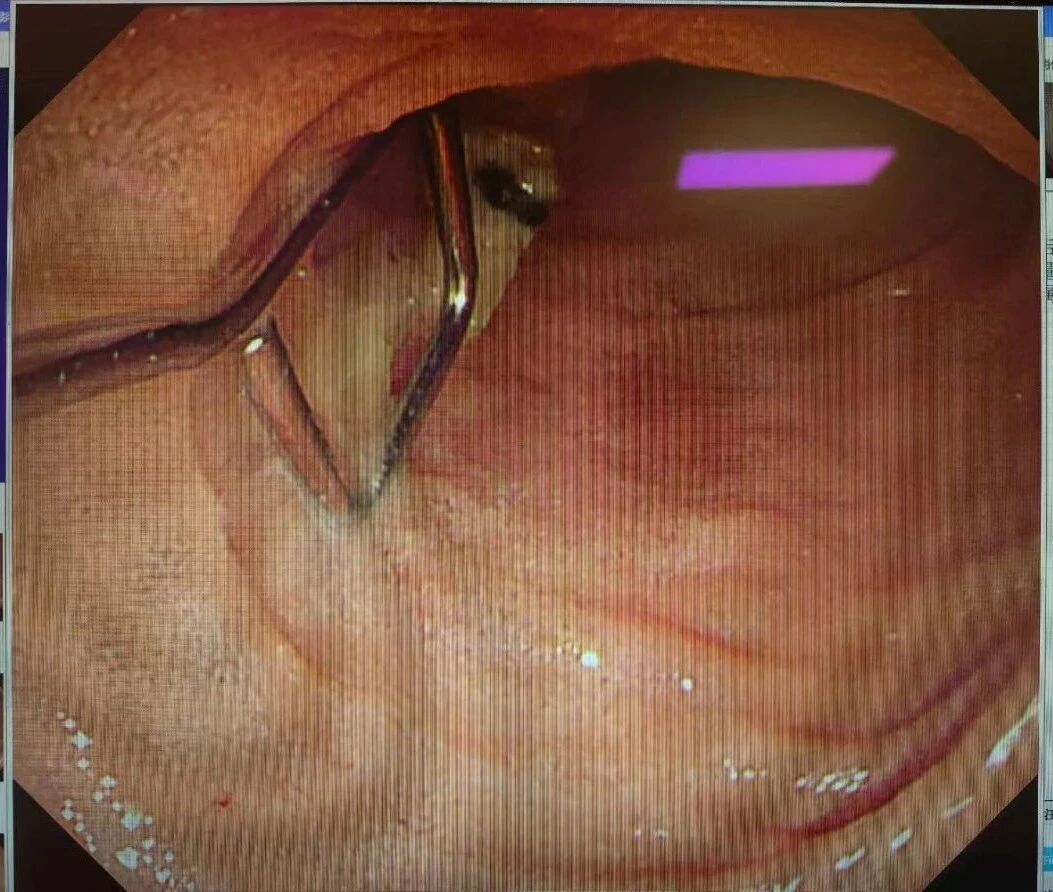

术中,杨丹丹医师通过治疗内镜进镜,发现患者食管入口及胃腔内有大量食物残渣,为寻找异物增加了难度。凭借精准的操作与丰富经验,她继续深入探查,最终在十二指肠降部成功定位那枚异型金属异物。杨丹丹小心翼翼地使用异物钳钳住异物尖端,将其稳妥脱入透明帽内,缓慢、平稳地将异物拖出体外,随后顺利退镜。

术中,杨丹丹通过治疗内镜进镜,发现患者食管入口及胃腔内有大量食物残渣,为寻找异物增加了难度。医护人员凭借精准的操作与丰富经验,继续深入探查,最终在十二指肠降部成功定位那枚异型金属异物。随后,杨丹丹小心翼翼地使用异物钳钳住异物尖端,将其稳妥脱入透明帽内,缓慢、平稳地将异物拖出体外,并顺利退镜。

(取出金属异物)